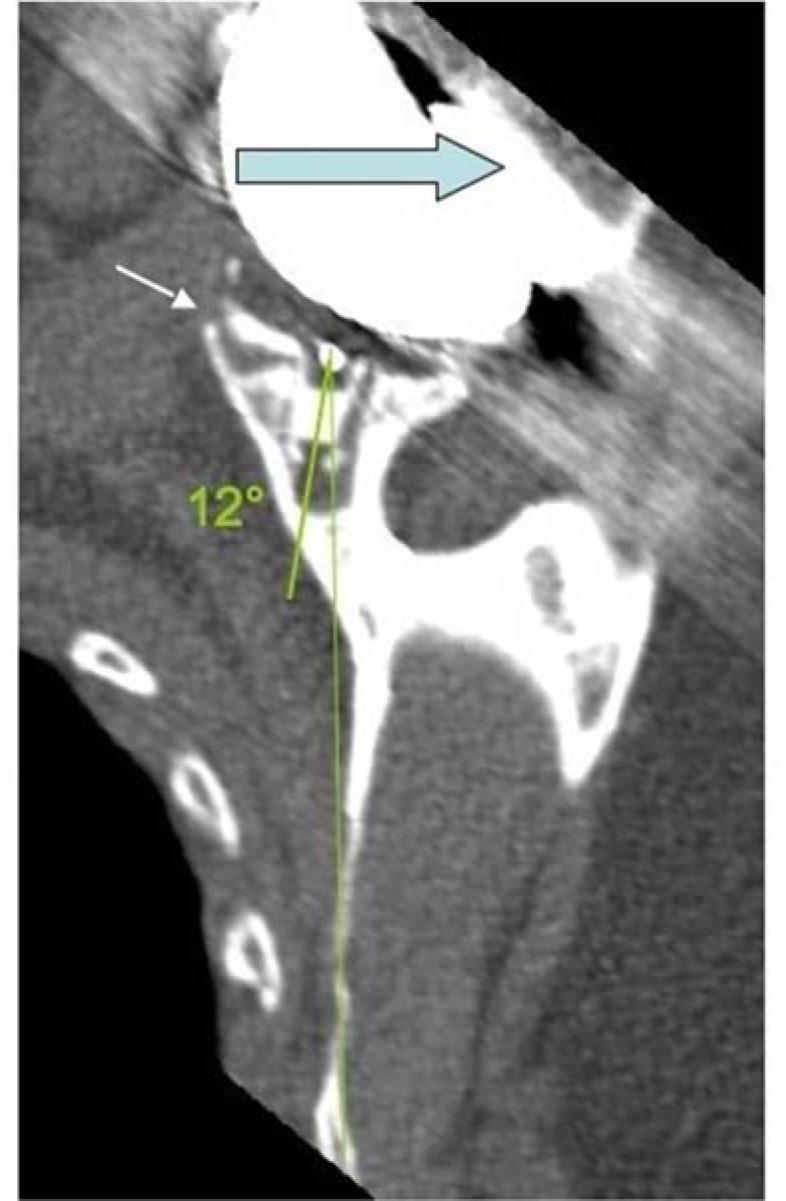

Total shoulder arthroplasty (TSA) is an effective approach for the treatment of a variety of clinical conditions affecting the shoulder, including osteoarthritis, inflammatory arthritis and osteonecrosis, and the number of TSA implanted has grown exponentially over the past decade. This review gives an update of the major complications, mainly infections, instability and loosening, encountered after TSA, based on a corpus of recent publications and a dynamic approach: The review focuses on the causes of glenoid loosening, which account for 80% of the complication, and underlines the importance of glenoid positioning in the recovery of early shouder function and in the long term survival rate of TSA.

全肩关节置换术(TSA)是治疗多种影响肩部的临床病症的有效方法,包括骨关节炎、炎性关节炎和骨坏死,在过去十年中,TSA植入数量呈指数级增长。基于最近的一系列出版物和动态方法,本综述对TSA术后出现的主要并发症(主要是感染、不稳定和松动)进行了更新:该综述重点关注占并发症80%的肩胛盂松动的原因,并强调肩胛盂定位在早期肩部功能恢复和TSA长期生存率中的重要性。